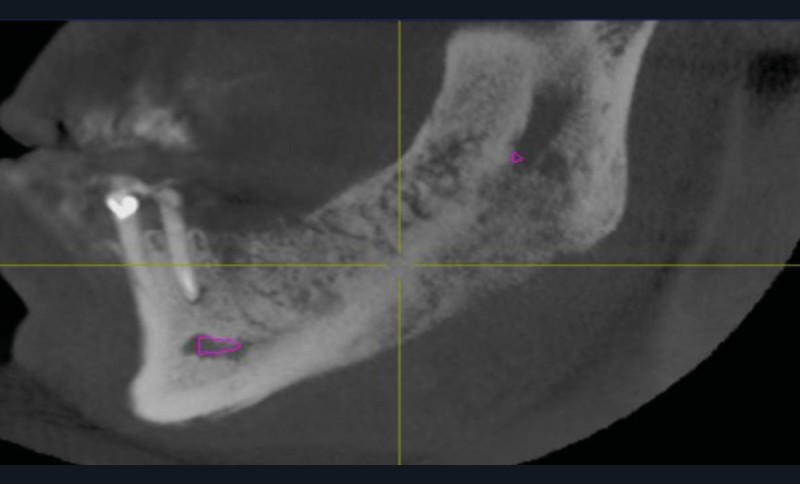

L’examen radiologique (scanner ou tomographie a faisceau conique) est très évocateur. Il montre un épaississement périosté avec « aspect mixte » de l’os médullaire et des « perforations corticales ».

L’ostéomyélite passe par plusieurs stades au cours de son évolution. Au début, les zones d’ostéolyse et de sclérose sont invisibles radiologiquement…